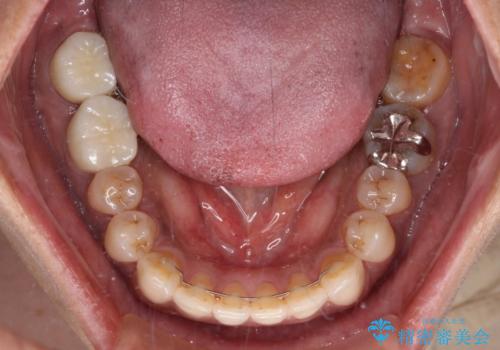

極端な上下前歯の開咬を改善 オープンバイトのインビザライン矯正

治療前に、いくらインビザライン矯正がオープンバイトを得意としているとは言え、さすがに限界があるだろうと思っておりましたが、前歯でレタスが噛めるまで改善することができました。

顔の印象も大きく変わり、患者様には大変満足していただきました。